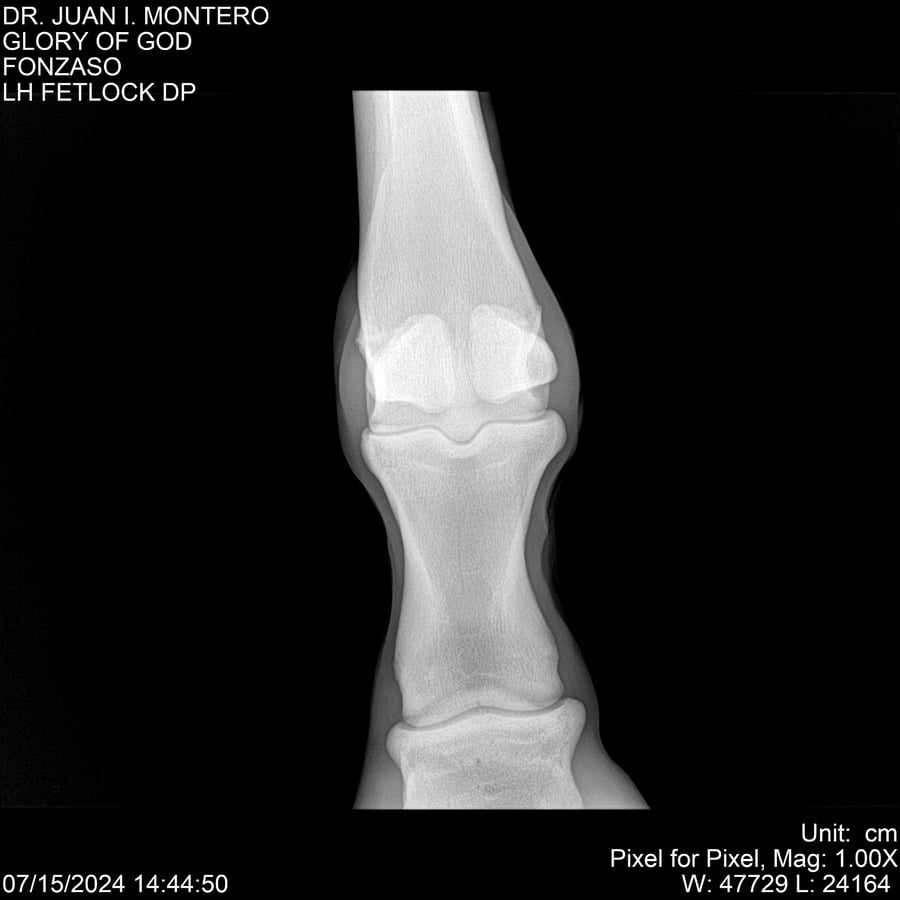

LOTE 10, GLORY OF GOD 🔥 🔥 🔥 Lote Anterior Volver al remate Lote Siguiente Ficha Contacto Montevideo - Ficha del Lote Identificador: #281389 Categoría: Yeguarizos Montevideo - 115 Visualizaciones ClicData Contacto Empresa: Abelenda N. R., Walter Hugo Nombre*: Teléfono* : E-mail* : Mensaje Enviar Registrese gratis Este contenido Exclusivo está disponible sólo para usuarios registrados Ingresar